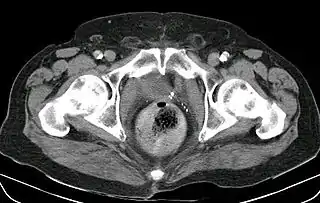

![]() Fecaloma rectal en un paciente hospitalizado. Presenta, además, una neovejiga y aterosclerosis. TC abdominal. | ||